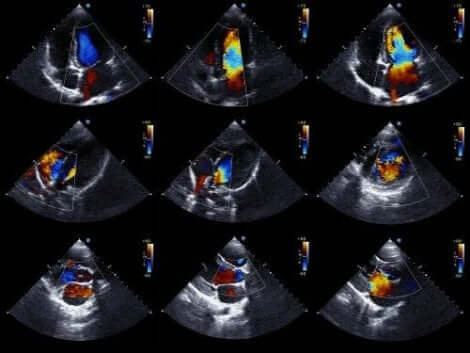

تخطيط صدى القلب هو الاختبار المفضل لاكتشاف الانصباب. وهو يسمح للأطباء برؤية هيكل القلب ودراسة قدرته على ضخ الدم.

مخطط صدى قلب دوبلر نوع من هذا الاختبار يسمح للأطباء أيضًا بتحديد سرعة تدفق الدم من القلب بدقة. من الناحية الفنية، المخطط ثنائي الأبعاد والتصواتي هو التقنية المثالية لتشخيص، قياس ومراقبة الانصباب.

العثور على غياب للصدى بين التامور والنخاب يسمح للأطباء بتشخيص الحالة. بعد ذلك، يحدد طبيب القلب مستوى الانصباب وفقًا لحجم المساحة بين الطبقتين.

من الجدير بالذكر هنا أن هناك نوعان أساسيان من تخطيط صدى القلب. يوجد التخطيط الصدري، حيث يتم وضع الجهاز الذي يولد الصوت على الصدر فوق القلب. ويوجد التخطيط المريئي، حيث يتم إدخال الجهاز في السبيل الهضمي حتى المريء، وهذا الاختبار يوفر المزيد من البيانات.